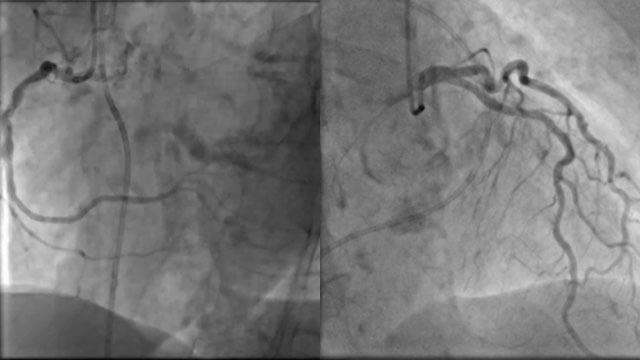

A challenging valve-in-valve scenario in a patient with prior aortic coarctation repair

A 79-year-old with a degenerated aortic bioprosthesis after complex coarctation surgery challenges conventional strategies. Which access route would you choose?